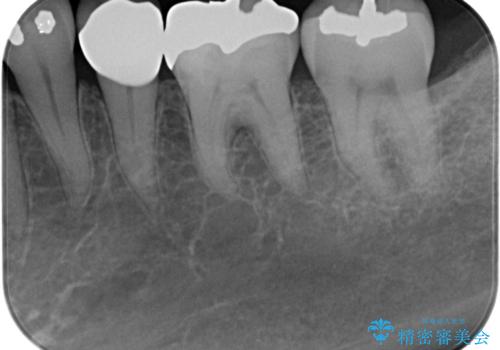

- 左下の奥歯に虫歯がある気がするとのことで来院された患者様です。

手前はジルコニアクラウンで白く、奥はゴールドアンレーでより適合の良いものを装着します。

銀歯の裏側に虫歯が確認されました。

小さな段差も虫歯のリスクにつながります。

精度の良い補綴物を入れることで今後の虫歯リスクを抑えることができます。